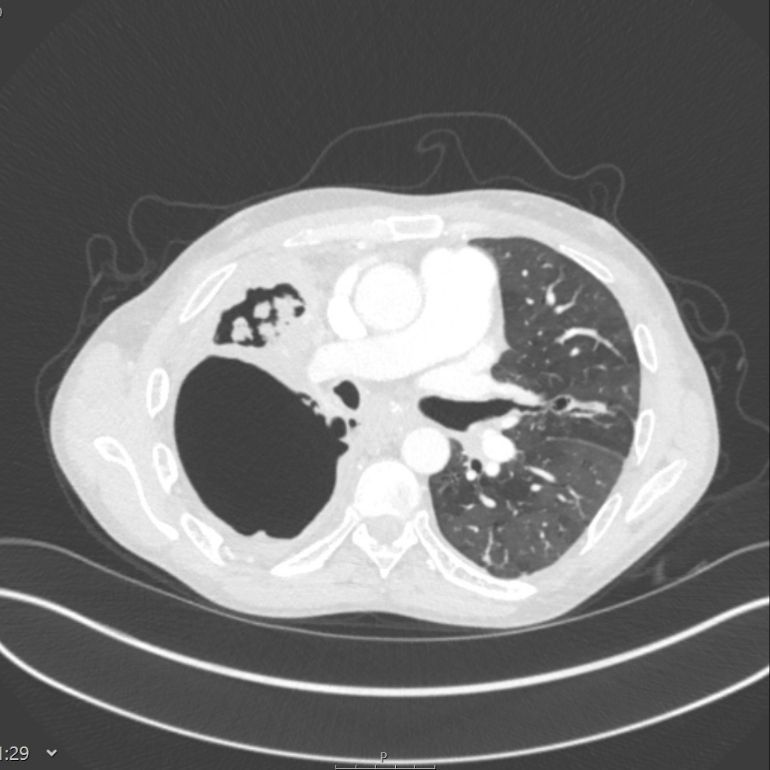

X-ray showing the lungs of a person with tuberculosis